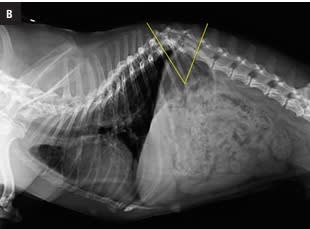

Este atlas de consulta rápida ayudará al clí­nico a obtener la máxima información de sus estudios radiográficos del tórax. Presenta gran cantidad de imágenes que guiarán al veterinario en su interpretación radiográfica, desde la misma técnica, la posición más idónea según la patologí­a que se sospeche o el estado clí­nico del paciente, o variaciones fisiológicas, hasta el órgano o estructuras torácicas a evaluar. Presenta montajes anatómico-radiográficos para ayudar a visualizar las estructuras que se están valorando en la radiografí­a. Aporta imágenes de las proyecciones radiográficas torácicas normales de más de 30 razas caninas para su comparación directa lo que hacen de este libro una guí­a de referencia de radiografí­as torácicas raciales.

Capítulo 1. Introducción. Capítulo 2. Indicaciones. Capítulo 3. Obtener la imagen radiográfica torácica. Técnica. Proyecciones. Capítulo 4. Factores fisiológicos que  pueden influir en la imagen radiográfica. Edad. Sexo. Condición corporal. Fase respiratoria. Ciclo cardíaco. Capítulo 5. La raza. Capítulo 6. Interpretación de la imagen  radiográfica. Límites torácicos. Vértebras. Esternón. Arco costal. Diafragma. Aparato respiratorio. Tráquea. Bronquios. Pulmones. Sistema cardiovascular. Corazón. Grandes  vasos. Vasos lobares. Mediastino. Esófago. Linfonódulos. Pleura. Capítulo 7. Radiografía torácica por razas caninas. American Staffordshire. Basset hound. Beagle. Boxer.  Bulldog Francés. Bull Terrier. Caniche Toy. Carlino. Cavalier King Charles Spaniel. Chihuahua. Cocker Spaniel. Dálmata. Doberman. Golden Retriever. Gran Danés. Husky Siberiano.  Labrador Retriever. Maltés. Mastín Español. Pastor Alemán. Pequeño Lebrel Italiano. Pinscher Miniatura. Pointer. Schnauzer Miniatura. Setter Irlandés. Shih Tzu. Teckel. Terranova.  Welsh Corgi Pembroke. West Highland White Terrier. 9Yorkshire Terrier. Índice analítico